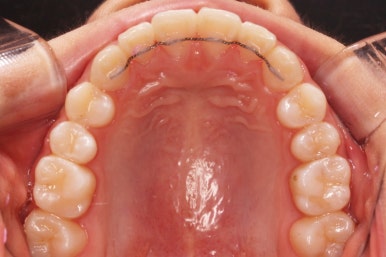

아래쪽이 더 시급하므로 브라켓 부착을 하여 가지런히 하기 시작했고 위쪽은 악궁확장장치를 입천장에 하여 위턱뼈를 가로로 넓혀주기 시작합니다.

악궁확장장치는 총 4-6개월 정도 부착하고 있으며 그 이후에는 입안에서 제거하게 됩니다.

윗니에도 이제 장치를 모두 붙였습니다. 아래쪽은 어느 정도 가지런해지고 나면 부족한 자리를 만들어주기 시작합니다.